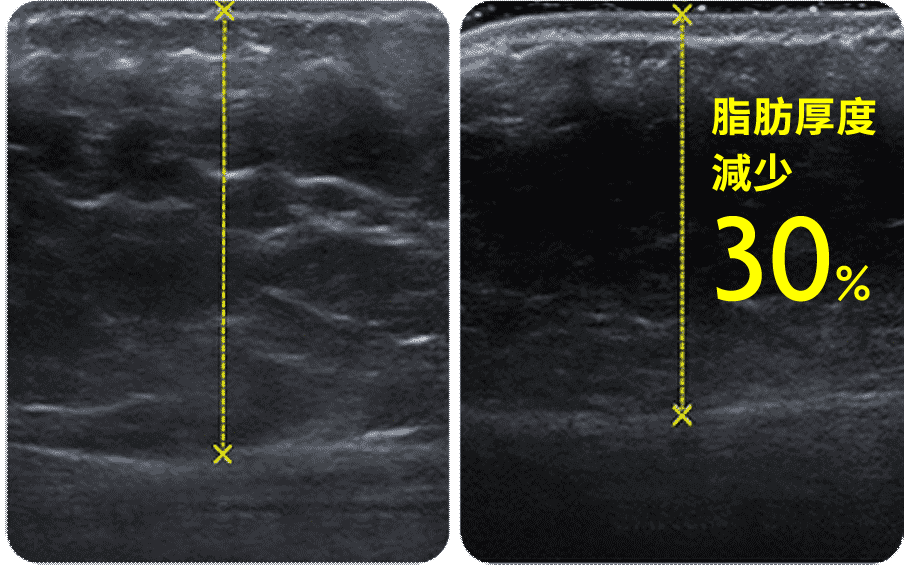

埋線減肥有效嗎?經研究證實1,埋線可以顯著降低體重、BMI、腰圍、臀圍、腹部皮下脂肪組織厚度(請看下面的超音波檢測圖。:.゚ヽ(*´∀`)ノ゚.:。)等肥胖指標,同時也能改善血壓、低密度脂蛋白過高等問題。